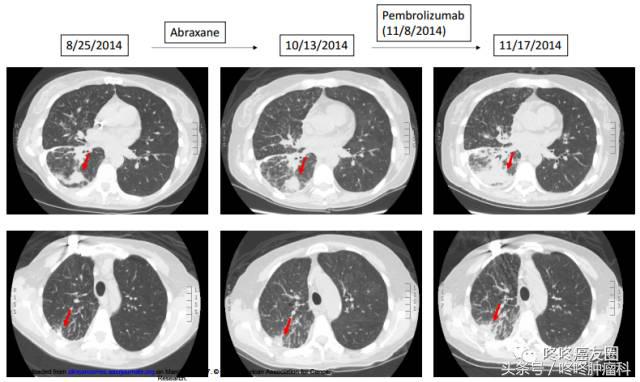

假进展,顾名思义,并不是真正的进展,实际还是有效的,指的是有些患者使用PD-1抗体之后,出现肿瘤先增大后减小的 “过山车”现象,如下图所示: